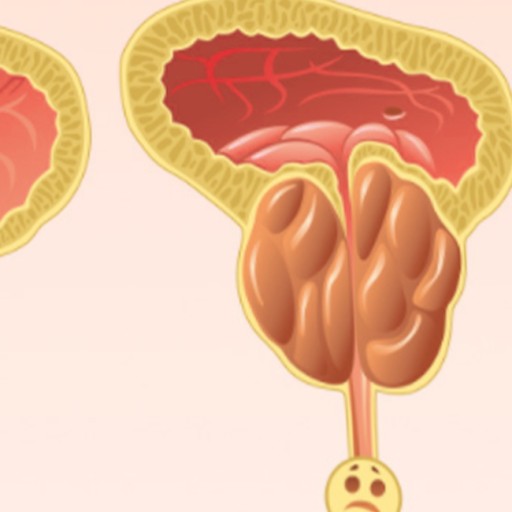

오늘은 남성에게 발생하는 주요 암 중 하나인 전립선암의 초기 증상에 대해 이야기하려 합니다. 전립선암은 초기에는 증상이 매우 미미하거나 전립선 비대증과 같은 양성 질환과 유사하여 간과하기 쉽습니다.

전립선암 초기증상 하지만 조기에 발견할 경우 치료 예후가 매우 좋으므로, 전립선 건강에 대한 작은 신호라도 놓치지 않고 관심을 가지는 것이 중요합니다. 특히 50세 이상 남성이라면 더욱 주의가 필요합니다. 지금부터 전립선암의 10가지 주요 초기 증상들을 꼼꼼히 살펴보고, 건강을 지키는 첫걸음을 함께 시작해 볼까요? 🚻

전립선은 방광 바로 아래에 위치하며 요도를 감싸고 있기 때문에, 전립선에 암이 발생하면 주로 소변(배뇨)과 관련된 증상들이 초기부터 나타나는 경우가 많습니다. 다음은 전립선암 환자들이 흔히 겪는 10가지 주요 초기 증상입니다.